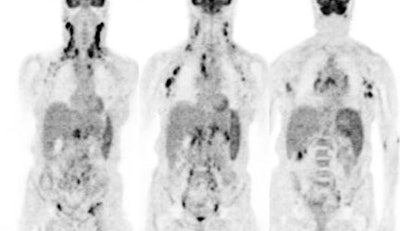

Diffuse splenic involvement: The patient shown below has non-Hodgkins lymphoma. The FDG PET exam demonstrated multiple sites of disease including diffuse involvement of the spleen, focal liver involvement, and persistent sites of adenopathy in the chest and abdomen. Case courtesy of Mercy Medical Center Alliance Imaging, Dr. Steve Allen. |

|

FDG PET imaging is more accurate than CT for the detection of lymphomatous involvement of the spleen [5,27]. On FDG PET imaging, diffuse or focal splenic uptake of greater intensity than the liver is felt to represent tumor involvement [27]. Infiltrative lymphomatous involvement of the spleen can be detected with a 67% increased frequency when compared with CT imaging [5]. Hepatic tumor involvement is characterized by focal or diffuse increased tracer accumulation [5].